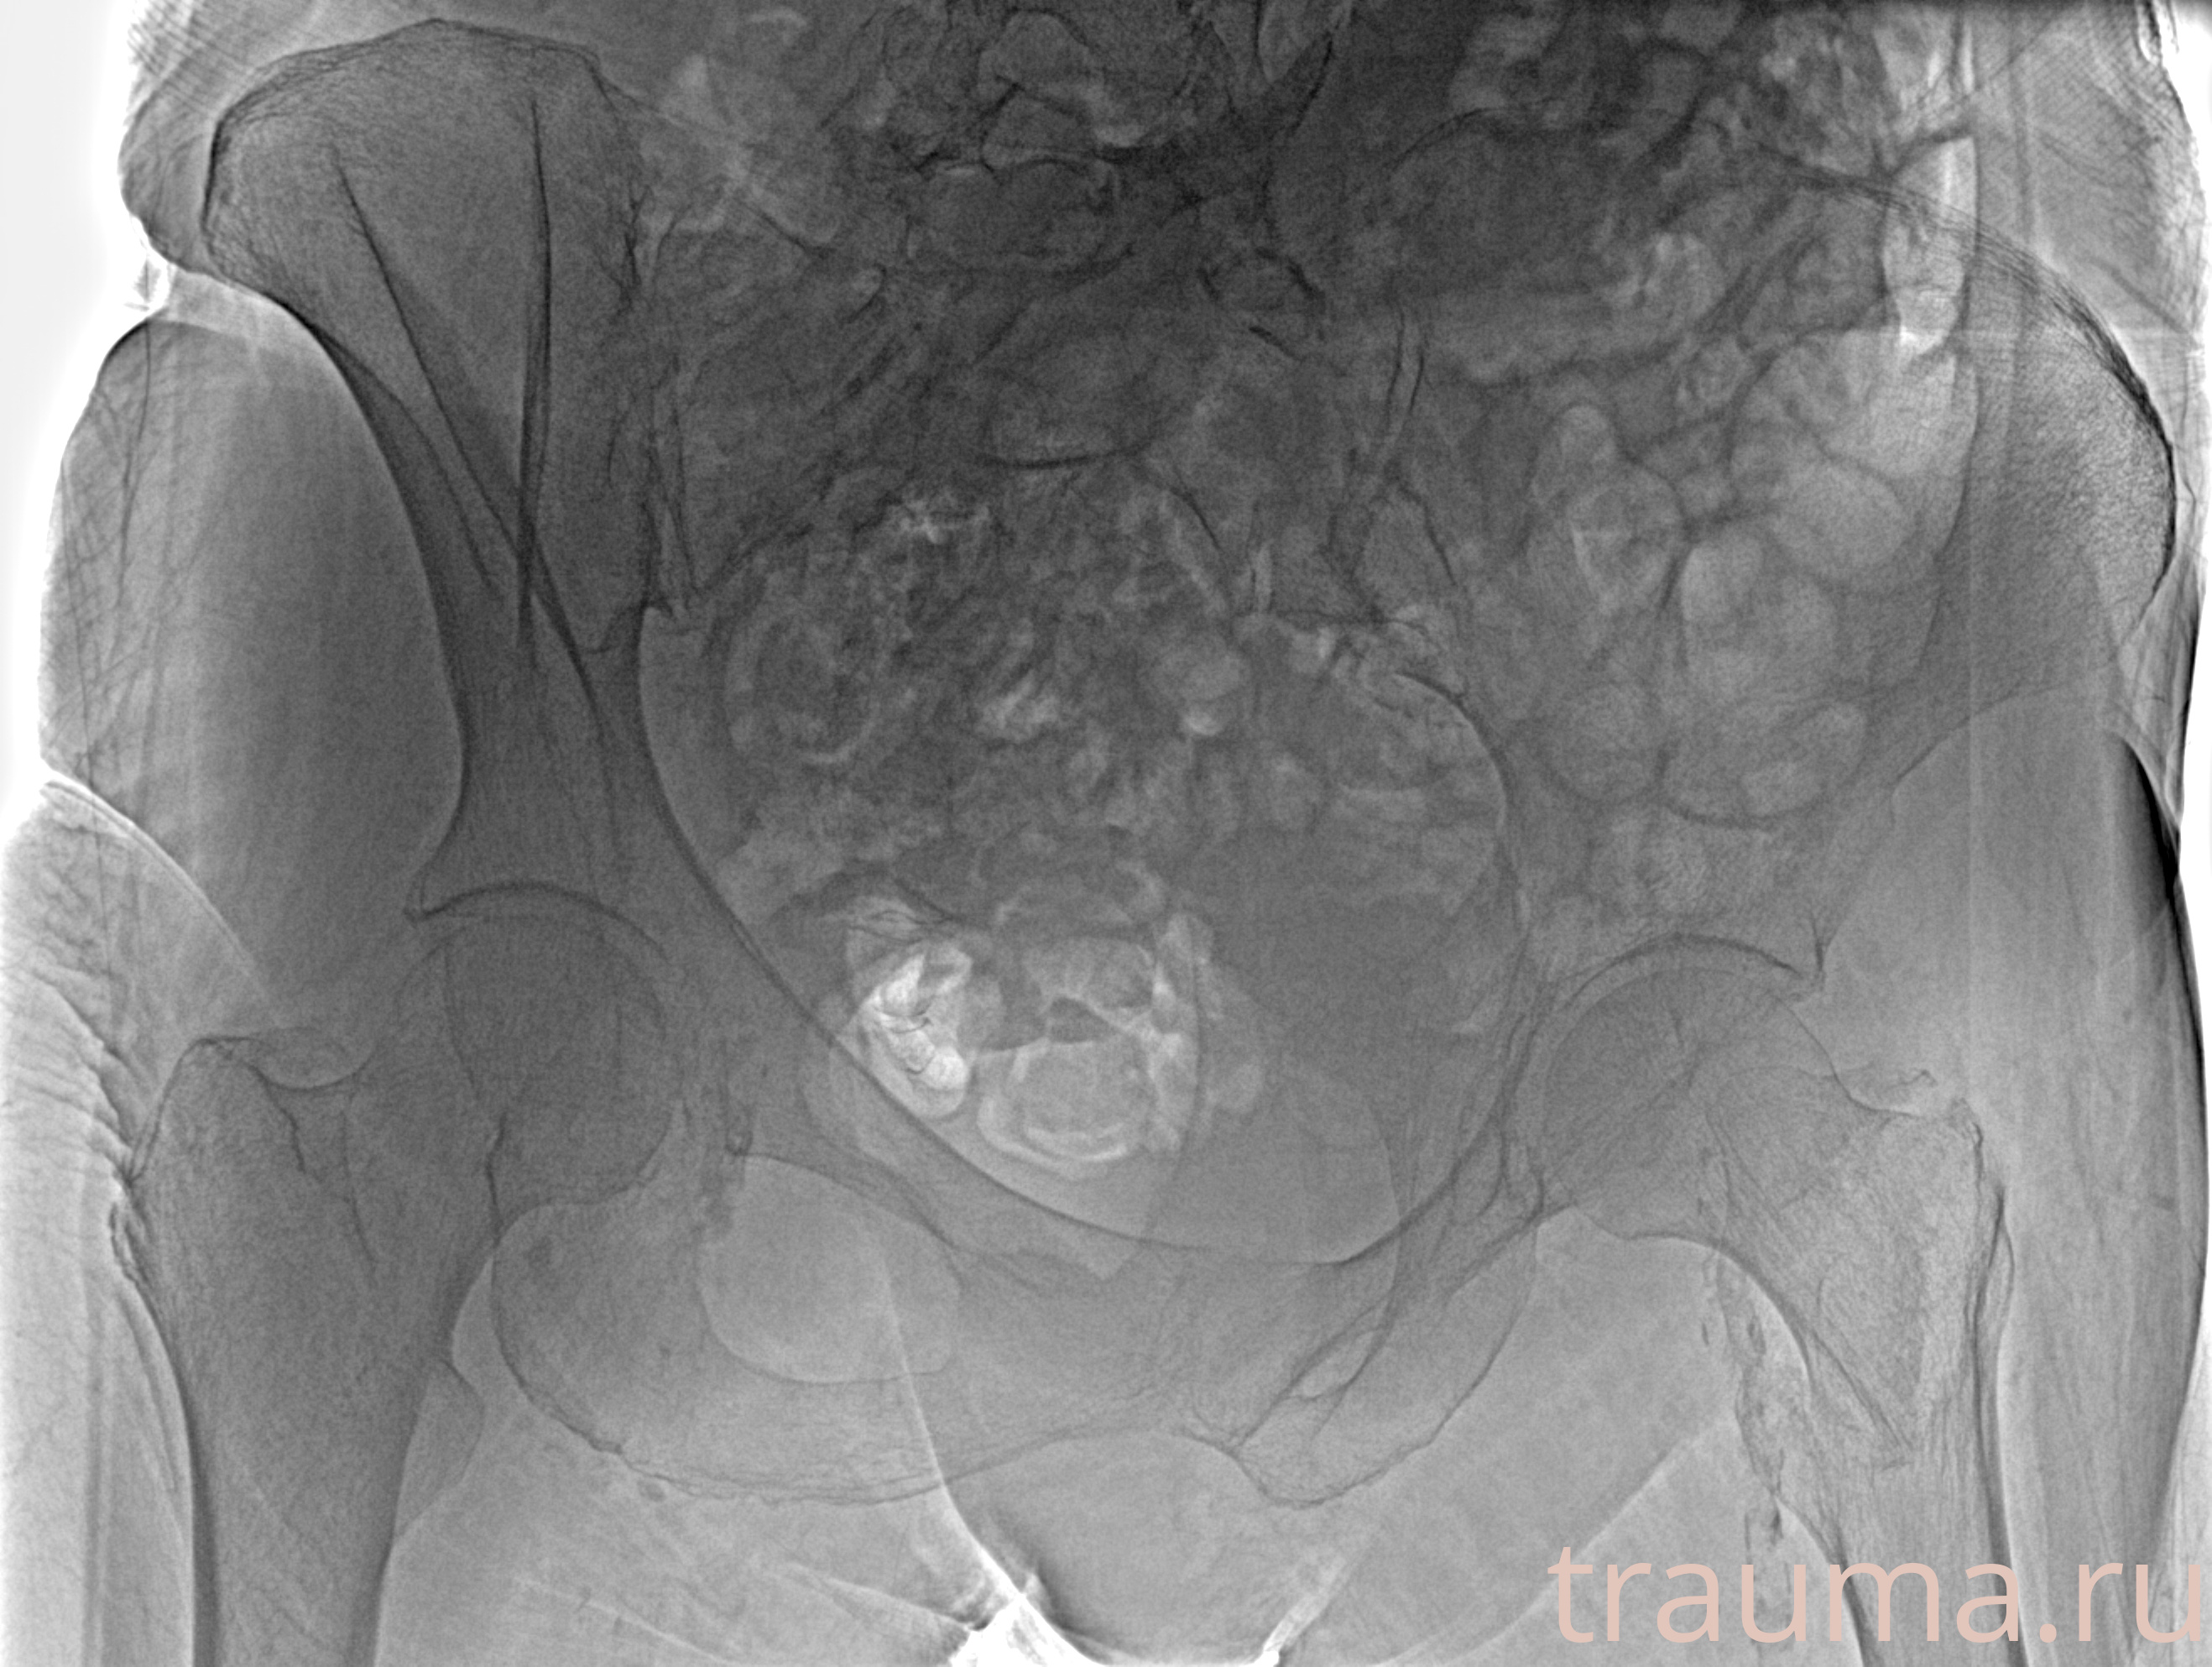

Рентгенограммы

Рентген на дому: по вашему адресу приезжает врач-рентгенолог, травматолог-ортопед с мобильным рентгеновским аппаратом, проводит диагностику травмы или заболевания, делает необходимые рентгенограммы, дает рекомендации по дальнейшему лечению. Получить качественные снимки в домашних условиях возможно благодаря уникальной методике, разработанной МосРентген Центром для института  Склифосовского